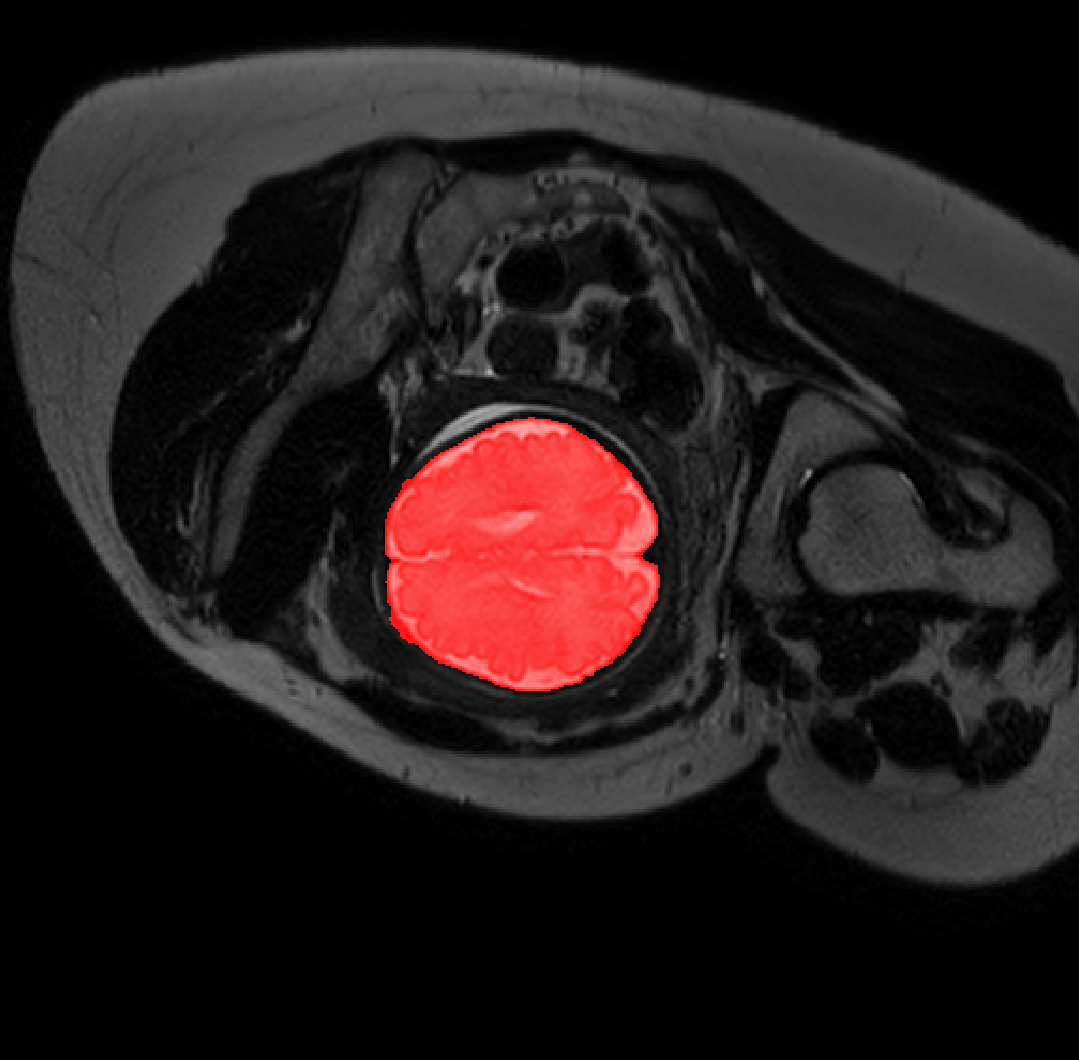

Table 1 lists average of quantitative evaluation results of these experiments and Figure 2 shows results obtained from each image. Figure 3 shows examples of the obtained segmentations.

Refer to caption

Figure 3: Example of ICV segmentations in images acquired in axial (left), coronal (middle) and sagittal (right) planes. Top row: A slice from T2-weigted image; Second row: Automatic segmentations obtained using 7 training images from the representative imaging planes; Third row: Automatic segmentations obtained using all 21 training images from all 3 image orientations; Bottom row: Manual segmentation.